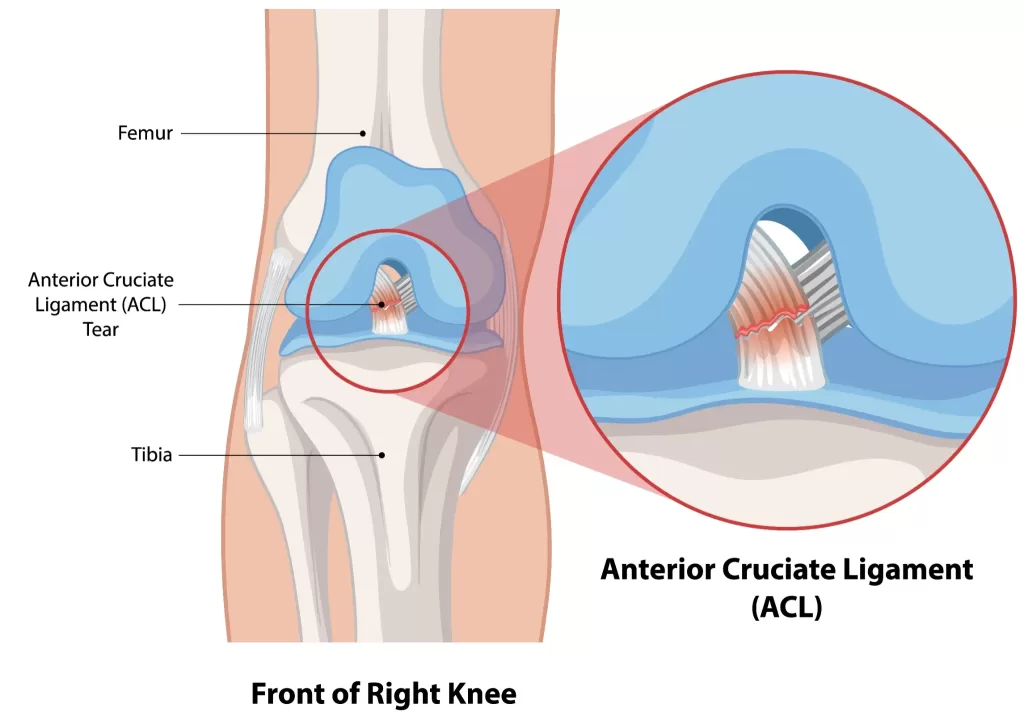

ACL Tear Treatment

Sports injury or sudden knee pain? An ACL tear is one of the most common causes of instability. Find out why. Read more